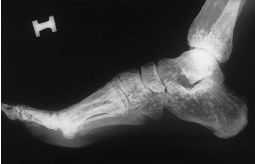

Se trata de unpaciente de 50 años de edad que acude a consulta pormolestias en las caderas desde hace semanas. La exploraciónfísica es normal, salvo una leve limitación en lasmaniobras extremas de la movilidad articular de ambascoxofemorales.

En la radiografía depelvis (fig. 1) se observan pequeños islotes decondensación diseminados por toda la pelvis. Algunosredondeados y lenticulares y otros de contorno irregular.Están muy bien delimitados en sus contornos y afectantambién al tercio superior de ambosfémures.

Figura1.